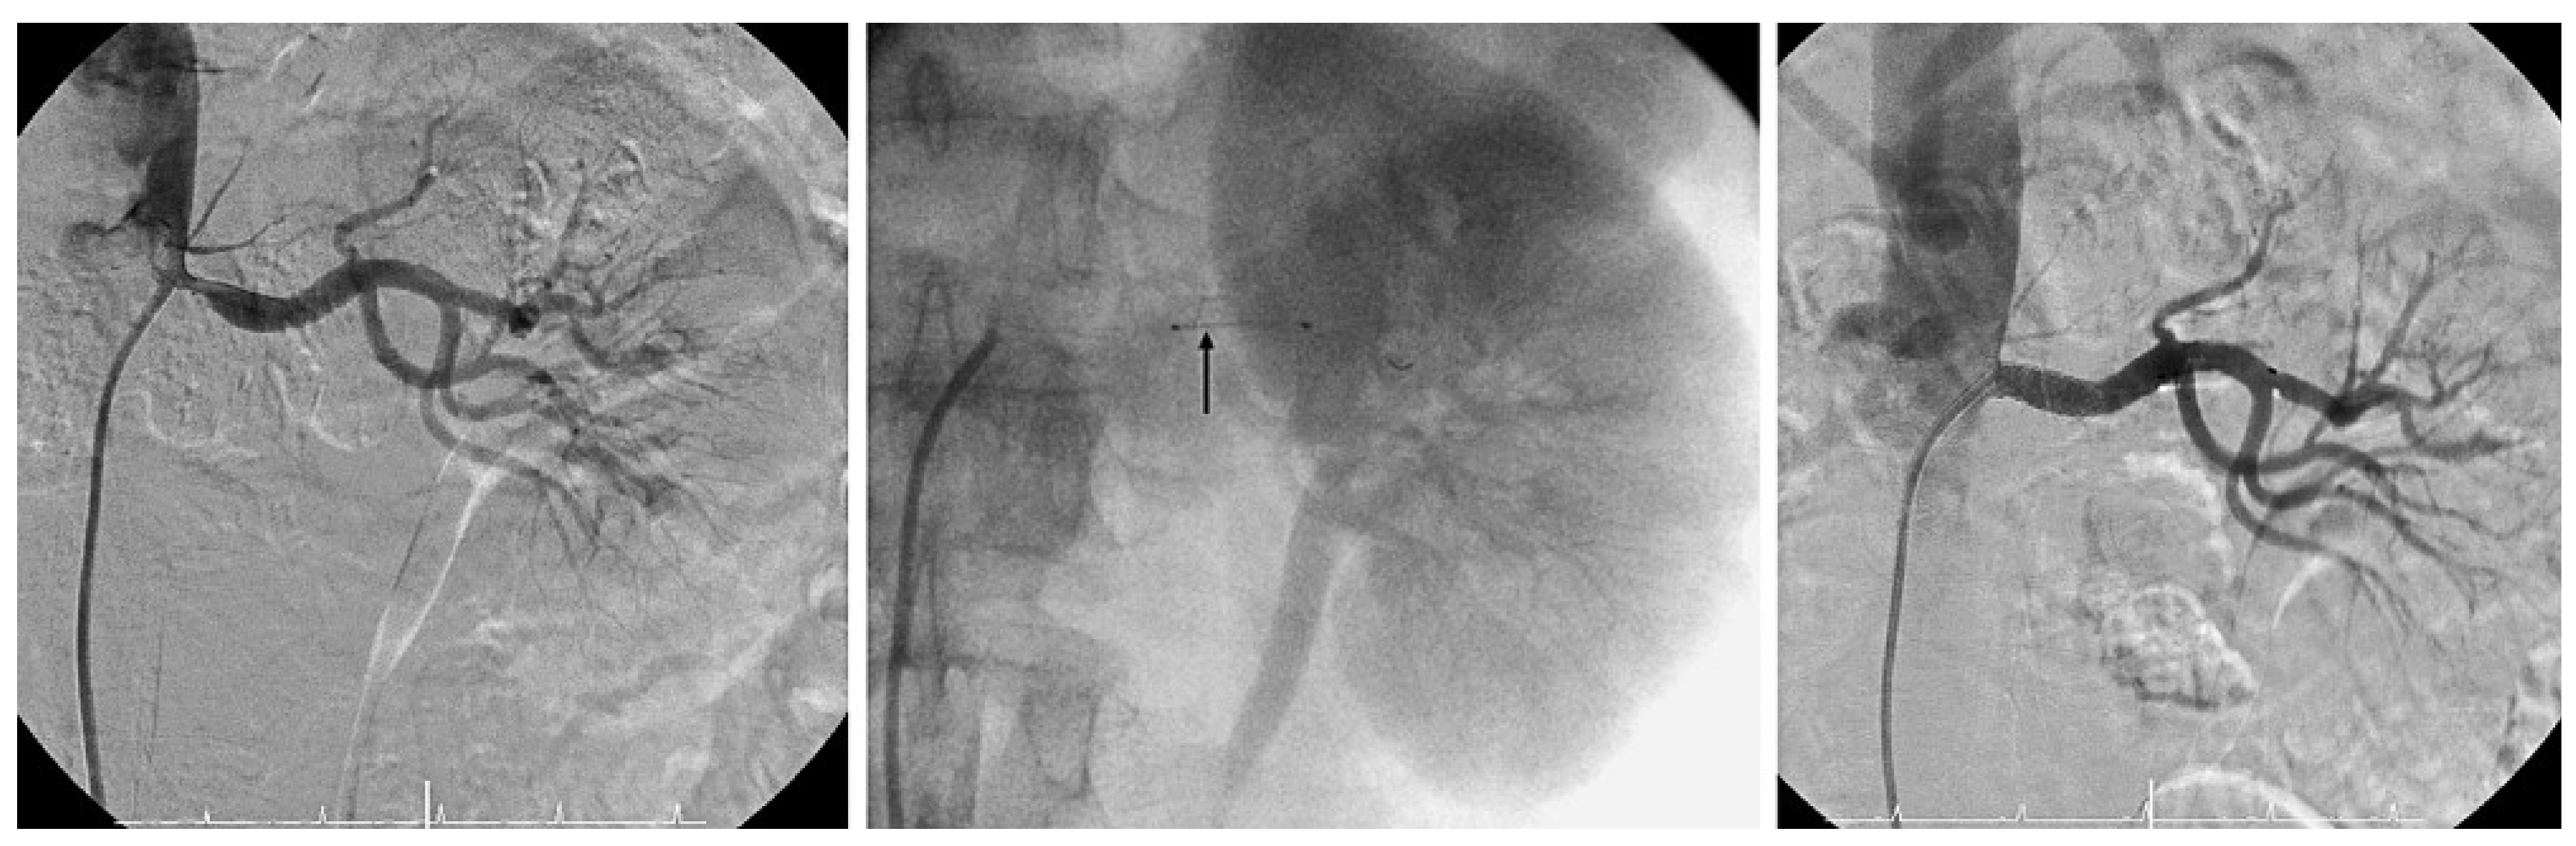

Carotid artery stenting

- Roffi, M.; Baumgartner, R.W.; Eberli, F.R. Images in cardiology. No reflow during carotid stenting. Heart (British Cardiac Society). 2006, 92, 538. [Google Scholar]